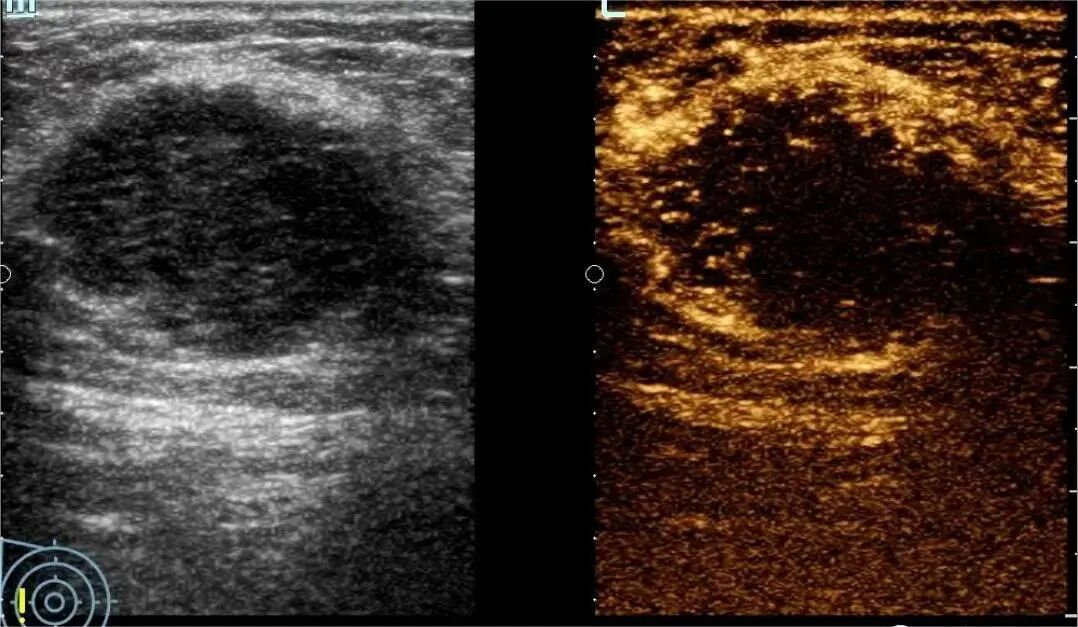

4月2日,贵州航天医院第55次晨读会由我院超声科医师敖春庆作学术交流,她以“中孕期产前超声筛查技术”为题,详细讲解了进修学习的成果,分享了科室实际开展的病例,阐述了未来的工作计划与展望,并结合典型病例图文分析等形式,强调了中孕期产前超声筛查的重要意义。 超声科专家简介 吴艳辉 中共党员,超声科学科带头人、主任,主任医师 临床擅长:从事超声诊断工作约30年,对心血管、小器官超声、超声引导下介入等具有丰富的临床经验。 骆科美 中共党员,超声科副主任医师 临床擅长:从事超声诊断工作33年,对胎儿心脏及颅脑、妇产超声、盆底超声等诊断具有丰富的临床经验。 胡大海 超声科副主任医师 临床擅长:从事超声工作17年,对心血管、外周血管、浅表器官超声诊断等具有丰富的临床经验。 刘 敏 超声科副主任医师 临床擅长:从事超声诊断工作20余年,对妇产科超声、心脏血管超声诊断具有丰富的临床经验。 敖春庆 超声科主治医师 临床擅长:对腹部、泌尿、妇科等超声诊断具有丰富的临床经验。 超声科简介 基本情况 贵州航天医院超声科配备多种超声检查设备(飞利浦彩超(IU-22、IU-Elite、HD11、Q5、Q7),迈瑞超声I9、DC-6、DC-8、GE-E8及床旁机,彩色超声诊断仪等),设有心血管诊室、妇产科诊室、腹部诊室、浅表小器官等检查室。 专科特色 四肢血管超声检查、双胎产前筛查及超声监护、超声造影检查技术、介入超声临床应用、经颅脑实质超声辅助筛查诊断帕金森病、女性性早熟超声诊断、盆底超声检查等。 NT超声检查 超声介入引导 肝脏超声造影 甲状腺造影 颅脑超声帕金森辅助检查 乳腺超声造影 上肢动静脉造瘘超声检查 双胎超声筛查 下肢血管超声检查 右心造影 诊疗范围 科室业务覆盖腹部、泌尿、妇科、产科(常规、NT筛查、III级筛查超声检查及高危妊娠监护)、成人心脏、外周血管、浅表器官(包含甲状腺、乳腺、阴囊、眼睛等)、颅脑(小儿颅脑、成人颅脑)、小儿肺超、造影、盆底、腹直肌、肌骨神经等检查及各种介入引导。 end